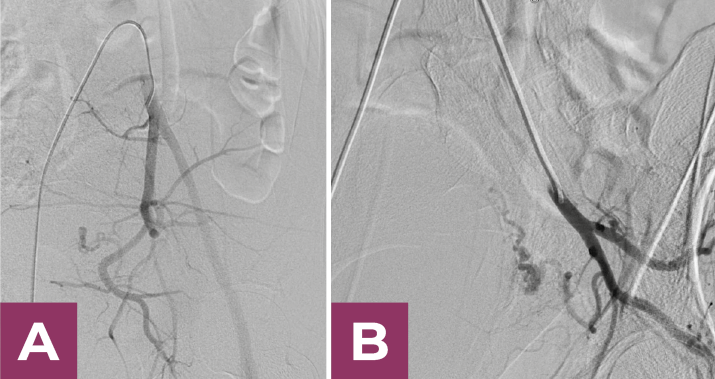

Laboratorios de ingreso: Hb: 8.2 g/dl, Hto: 24.6 %, Leucocitos: 12.200. No asoció datos de coagulopatía. Valorada por el servicio de Ginecología con estudio de control con datos de posible malformación uterina. En el estudio de AngioTc se aprecia engrosamiento miometrial importante con neoformaciones vasculares en la topografía de la pared uterina lateral izquierda; dependientes de la arteria uterina izquierda, los cuales se constatan en la angiografía pélvica. La malformación arterio-venosa (MAV) documentada es un ovillo redundante con dilataciones pseudoanuerismáticas dependientes de la arteria uterina izquierda. Angiotomografía Computarizada documenta la presencia de ovillo vascular en pared uterina lateral izquierda.

Posterior a la arteriografia diagnostica, la paciente fue sometida a embolización arterial distal supraselectiva de la arteria uterina izquierda con micropartículas Contour 250-355 y 355-500 micras y embolización arteria proximal con Squid 34 LD.

Se obtiene un resultado satisfactorio, con exclusión vascular y cierre completo y enérgico de la MAV izquierda.